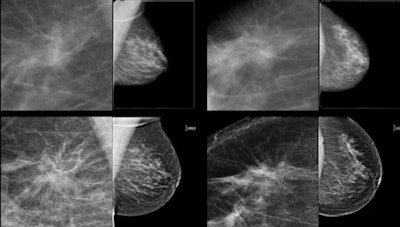

Subtle mass that was not recalled during screening, but detected on CAD. Top row: Exams that were not recalled during screening. Bottom row: Exams where lesion was detected in a later screening round. All images courtesy of Dr. Jaime Melendez.